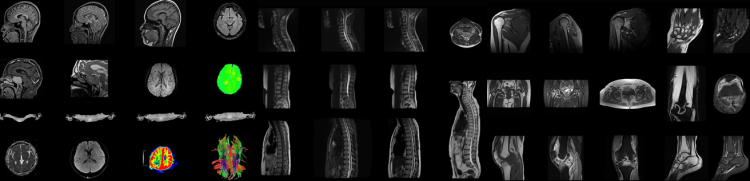

ANKE supermark 1.5T Wide Bore, derin öğrenme tabanlı AI yeniden yapılandırma teknolojisi ile görüntü kalitesini iyileştirmeyi ve tarama süresini kısaltmayı sağlamanın yanında geniş delik açıklığı, yumuşak ses teknolojisi ve tek severlik konumlandırma gibi özellikleri sayesinde hasta için rahat muayene sunarken hızlı iş akışı sağlamaktadır.

ANKE Supermark 1.5T Wide Bore, mıknatısın homojenliğini iyileştirerek yağ dokularının bastırılmasını sağlarken daha geniş FOV ve merkez dışı görüntüleme için mükemmel görüntü kalitesi sunar. Aktif, pasif ve 3D dinamik shimming teknolojisi gibi teknikleri benimseyerek görüntü kalitesini iyileştirir.